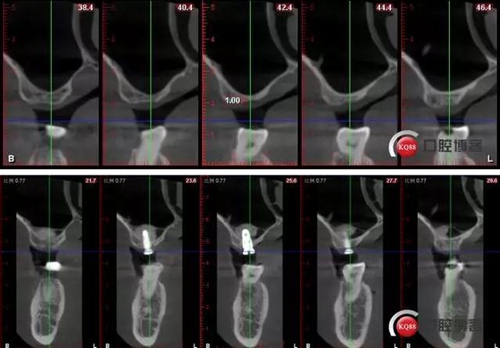

術(shù)后CBCT

術(shù)前術(shù)后CBCT對比:

打入0.2ml生理鹽水,回吸有血,已穿入上頜竇腔,再打入0.5ml,回吸0.2ml,打入1ml,回吸0.5ml,打水要溫柔

捏住患者鼻孔,囑發(fā)”嗡“的聲音,輕輕發(fā),可見植體窩內(nèi)血平面顫動,無氣泡溢出,竇膜完整